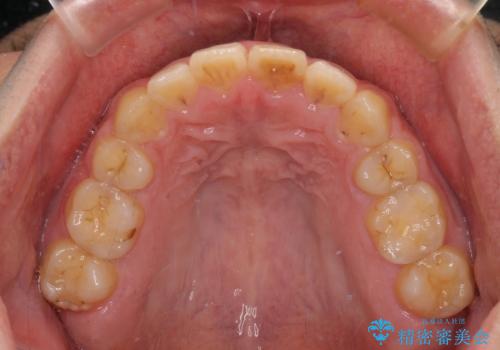

後戻りでデコボコの前歯 インビザライン矯正治療

- 高校時代に行った抜歯矯正が後戻りをしたとのことで来院された患者様です。

再矯正であることから、目立ちにくい装置を希望されたため、インビザラインにて矯正治療を行うこととしました。

下顎骨が左側に変位しているため、正中が合わないことは予想できましたが、歯列が整った後も咬み合わせが安定せず、咬み合わせを落ち着かせるために1年以上の期間を要しました。

噛みにくさの改善に時間がかかってしまうことがインビザラインの欠点の1つといえます。